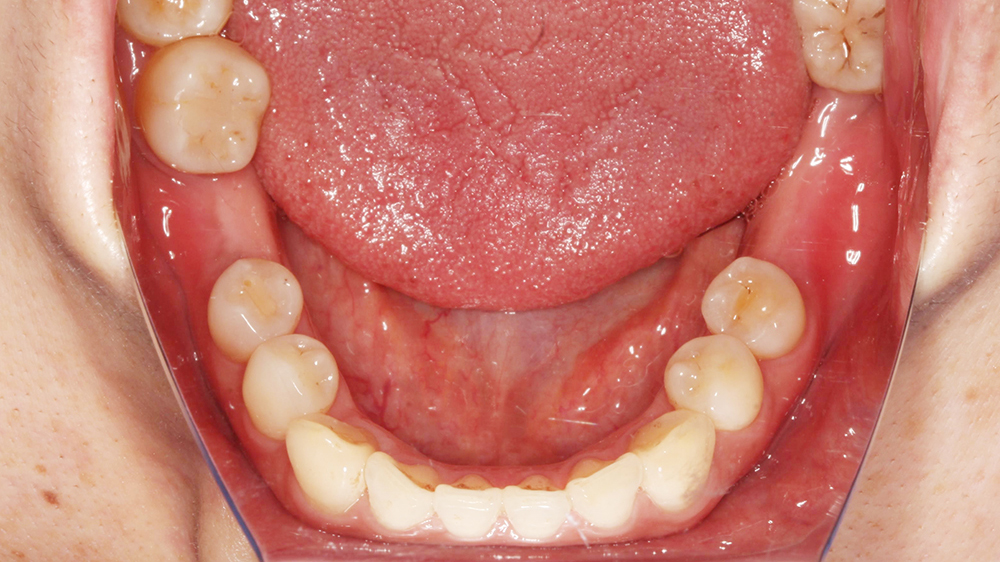

在術前規劃會使用數位化設計軟體,利用數位印模和數位排牙,精準地設計未來的牙齒排列和咬合狀態,更能真實模擬未來正式假牙效果,讓假牙設計既貼合個人需求,也更接近理想的美觀與舒適。

數位排牙可以預先模擬出手術後的效果,方便跟患者溝通,有任何想調整的地方也可以事先討論,讓整個過程更安心、更有把握。

醫師置入植體後,等待骨癒合完成會讓植體露出來,進行數位印模,並交給數位牙技師製作正式假牙。